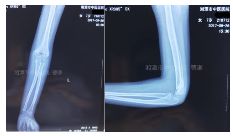

入院拍片如下:

四步复位法整复后拍片复查

治疗三周后拍片复查见骨痂生长

患者21个月后随访拍片复查情况如下: